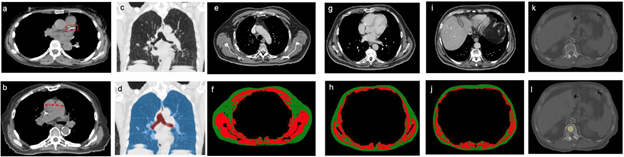

Fintelmann and team’s retrospective study included 282 patients (168 female, 114 male; median age, 75 years) with stage I lung cancer treated with SBRT between January 2009 and June 2017. To quantify CAC score and PA-to-aorta ratio, as well as emphysema and body composition, pretreatment chest CT was used. Associations of clinical and imaging features with overall were quantified using a multivariable Cox proportional hazards (PH) model.

For stage I lung cancer patients treated with SBRT, CAC score, PA-to-aorta ratio, and skeletal muscle index showed significant independent associations with overall survival. (p<.05). The model including clinical and imaging features demonstrated better discriminatory ability for 5-year overall survival than the model including clinical features alone (AUC 0.75 vs. 0.61, p<.01).